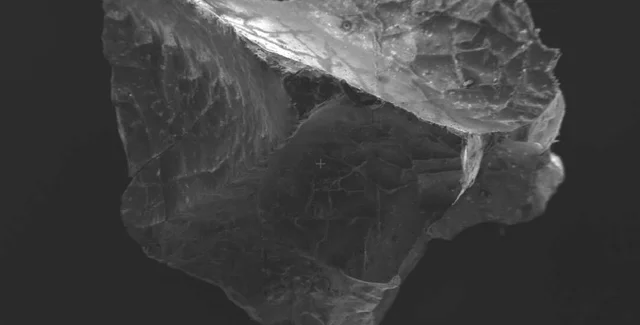

Фото: Pier Paolo Petrone

Используя растровый электронный микроскоп и передовые инструменты обработки изображений, команда изучила остекленевший мозг и обнаружила в нем ряд отдельных структур.

"Обнаружение остекленевшего мозга действительно редкое событие, но наличие в нем всей центральной нервной системы, состоящей из нейронов и аксонов, совершенно поразительно", – говорит Петроне.